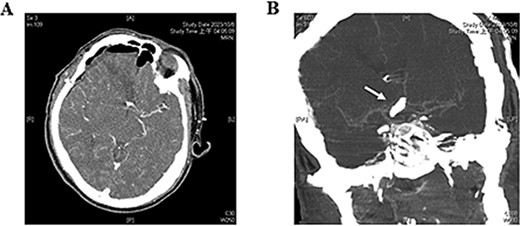

Four hours postoperatively, the patient experienced a generalized tonic–clonic seizure, requiring emergency intubation and sedation. Emergent post-operative brain computed tomography angiography confirmed that the right A1 segment was patent with no signs of intracerebral hemorrhage (ICH) or extradural hematoma (Fig. 3). Brain MRI, however, revealed a new infarction in the RAH territory (Fig. 4). To enhance perfusion, we maintained the blood pressure with a mean arterial pressure >65 mmHg and provided adequate hydration using normal saline. Antiepileptic medication was administered with levetiracetam 500 mg every 12 hours. Antiplatelet or anticoagulant medications were not given.

Postoperative brain computed tomography angiography. (A) No immediate signs of intracerebral hemorrhage or epidural hematoma are observed. (B) The patency of the A1 segment (white arrow) of the ACA is confirmed.